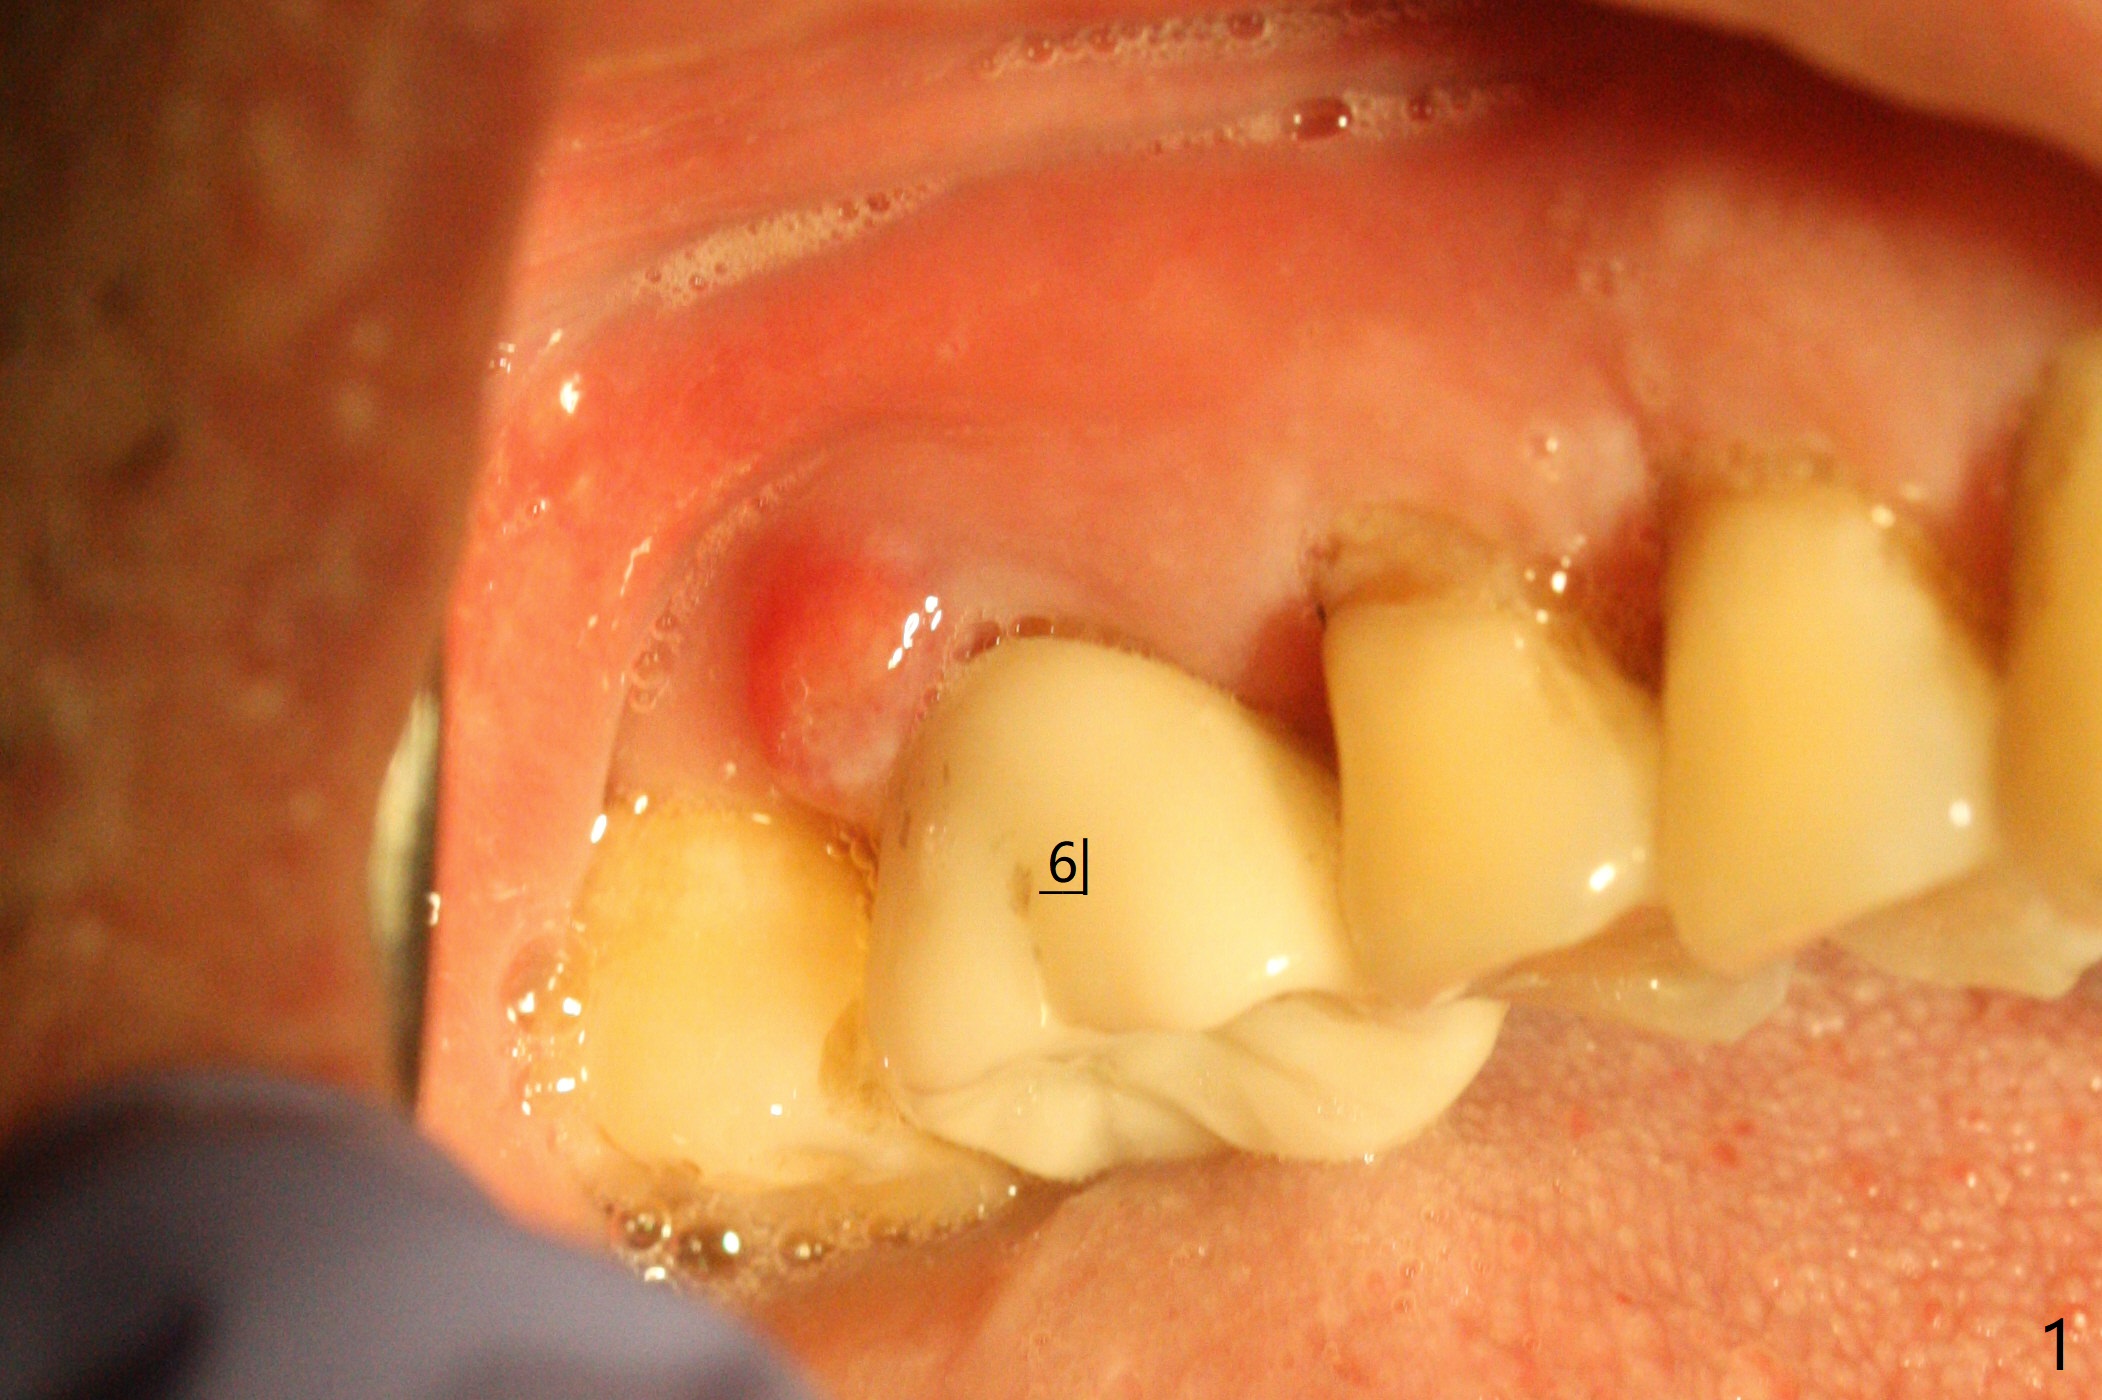

60岁男右上6出现脓包(图一),颊侧牙周袋深9毫米,指向近中颊侧根尖,根尖片(图二)和CT(图三(去除牙冠后))显示巨大近中颊侧根周骨质吸收,但是松动度低,一度想做根切。最佳植牙位点偏远中腭侧(图四),植体偏小,稳定性差,使用临时基台制作牙合面低的临时牙冠,目的包括固定粘性骨粉和防止邻牙移位。半张PRF膜用于上颌窦提升,另外半张用于覆盖牙槽窝开口的骨粉。局部使用抗菌素(Arestin),十九天后瘘道消失,根切,植骨可能成功。